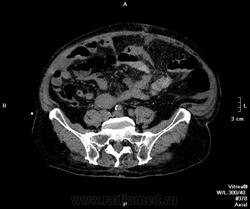

Пациент поступил ко мне через 6 дней после ушивания перфоративной язвы ДПК. УЗИ-сты увидели инфильтративно-жидкостные изменения в зоне оперативного вмешательства, пузырьки газа. Но смутило найденное образование в пространстве между правой долей печени и паранефрием. цель исследования - дифференцировать найденное между инфильтрацией и жидкостным скоплением.

Пациента готовили в течение 2 часов, перорально разведенный урографинчик дробно, и пол станканчика перед исследованием (это важно). Болюс в артериальную и венозную фазы.

мы имеем - задренированное околопеченочное пространство, жидкость в подпеченочном, левом поддиафрагмальном пространстве и по контурам селезенки (серозная), к передне-наружному контуру левой доли печени прилежит ограниченное жидкостное скопление

-ничего криминального между висцеральной поверхностью печени и правой почкой (паранефрий как им угодно) не вижу

-!!! в нативе желудок и петли кишечника не контрастированы - следы контраста в отдельных петлях тонкого к-ка (перед исследованиям он пил, по зонду ничего никуда - ни ни!!!), петли толстого и тонкого кишечника содержат умеренно повышенное количество воздуха и жидкого содержимого, с горизонтальными уровнями

- просвет верхне-горизонтальной ветви дпк в области оперативного вмешательства и зоны сегментарной пластики убудительно не прослеживаеся, представлен зоной инфильтрации, утолщенными стенками кишки, по наружному контуру воспаленных тканей лентовидно расположенные пузырьки воздуха - более вероятно воздух на фоне складок; затеков КВ нет

- воспалительные изменения в проекции лапаротомного доступа, в пжк передней брюшной стенки, в абдоминальной жировой клетчатке и межпетельно

- диверткулище мочевого пузыря

- инфильтрат в левой седалищно-прямокишечной ямке

- меня смущает не типичный вид артериальной фазы, и уж тем более венозной

Усиление коркового вещества слабое, задержка начала нефрографической фазы. диаметр почечным артерий около 5 мм, почечных вен -- 10мм. на 60 секунде отсутствует должное конрастирование вен, без признаков патологического сброса

и куда контраст делся из кишечника? (предположим - не развели в кувшинчике, но выпить-то перед исследованием мы ему дали)

ну не глюк ведь??? ни одна вена не усиливается! почему так???